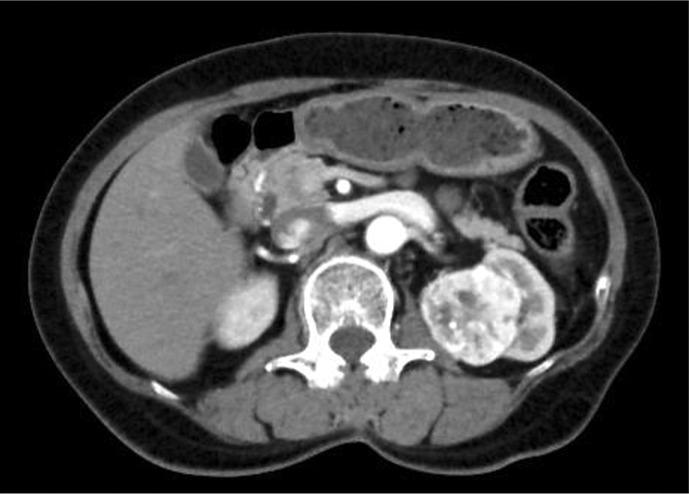

Case presentation: A 76-year-old woman who underwent radical nephrectomy for clear cell RCC (pT1bN0M0 Grade 3 INFb) at the age of 67 years presented to our hospital after her family doctor noted a pancreatic tumor. She was diagnosed with pancreatic metastasis of RCC based on histopathological examination, and avelumab and axitinib combination therapy was initiated. She developed irAEs, including myasthenia gravis, myositis, and myocarditis, which were treated with steroid pulse therapy. The patient recovered after treatment and was discharged without sequelae.